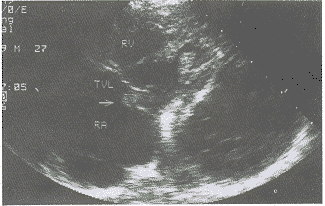

彩超检查所见:右室内径(31mm),右房内径(56×56mm)、均扩大。余房、室径大小正常,房室间隔连续完好,室间隔及左室后壁厚度、运动正常,右房内上腔静脉入口处可探及35mm×16mm的团块状回声,附着面广,回声较均匀,活动较小;三尖瓣后瓣可探及附着于其上的21mm×13mm的团块状回声(图1、2),活动较大,右室前壁中部近乳头肌位置探及团块回声(图3),活动较差。收缩期于右房内探及分布中等的三尖瓣五彩返流束。彩超提示:1、右心占位病变(提示血管肉瘤);2、右房室多发性粘液瘤;3、三尖瓣返流(中度)。

图1 RA内近三尖瓣处一团状回声

图2 箭头示三尖瓣后瓣一团块状回声